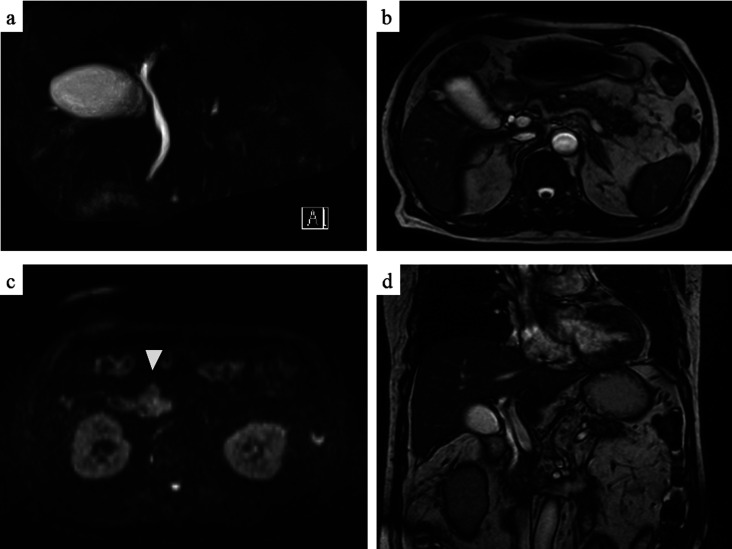

Objective: Since the onset of the coronavirus disease 2019 (COVID-19) pandemic, COVID-19 vaccination has substantially reduced mortality and hospitalization rates worldwide, with rare adverse events reported in clinical settings. Herein, we present a case of acute pancreatitis complicated by diabetic ketoacidosis (DKA) following the third COVID-19 vaccination dose. Patient: A 72-year-old male with a history of diabetes mellitus developed generalized fatigue, mild epigastric pain, nausea, and frequent vomiting after receiving the COVID-19 vaccine. Results: Blood analysis revealed elevated levels of pancreatic enzymes, hyperglycemia, and acidemia. Computed tomography revealed evidence of acute pancreatitis, leading to a diagnosis of both DKA and acute pancreatitis. Treatment with a large volume of saline and intravenous insulin improved both DKA and acute pancreatitis. After a thorough examination, no other factors capable of causing acute pancreatitis were identified. Hence, we concluded that acute pancreatitis was induced by COVID-19 vaccination. Conclusion: Acute pancreatitis is a rare but potentially life-threatening adverse event associated with COVID-19 vaccination. Delaying the treatment or diagnosis of acute pancreatitis can increase mortality risk in patients with both acute pancreatitis and DKA. Hence, it is crucial for healthcare professionals to consider the potential occurrence of acute pancreatitis and DKA following COVID-19 vaccination.